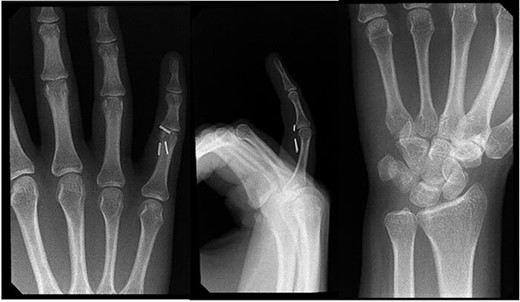

Four months postoperatively, the patient presented with complaints of pain at her small finger distal interphalangeal joint, and verbalized feeling small staples at the symptomatic site. Radiographic imaging demonstrated that the three previously placed hemoclips had migrated along the flexor tendon tract to the volar aspect of her right small finger proximal interphalangeal joint (Fig. 3). Surgical excision of the clips involved utilizing a Bruner-style incision volarly followed by a small window into the tendon sheath. One hemoclip was identified at the level of the proximal interphalangeal joint sandwiched between the flexor digitorum profundus and the superficialis tendons. Two more clips were identified proximally.

Right hand imaging 4-months status post revision CTR demonstrating symptomatic triple hemoclip migration into the volar aspect of the small digit.